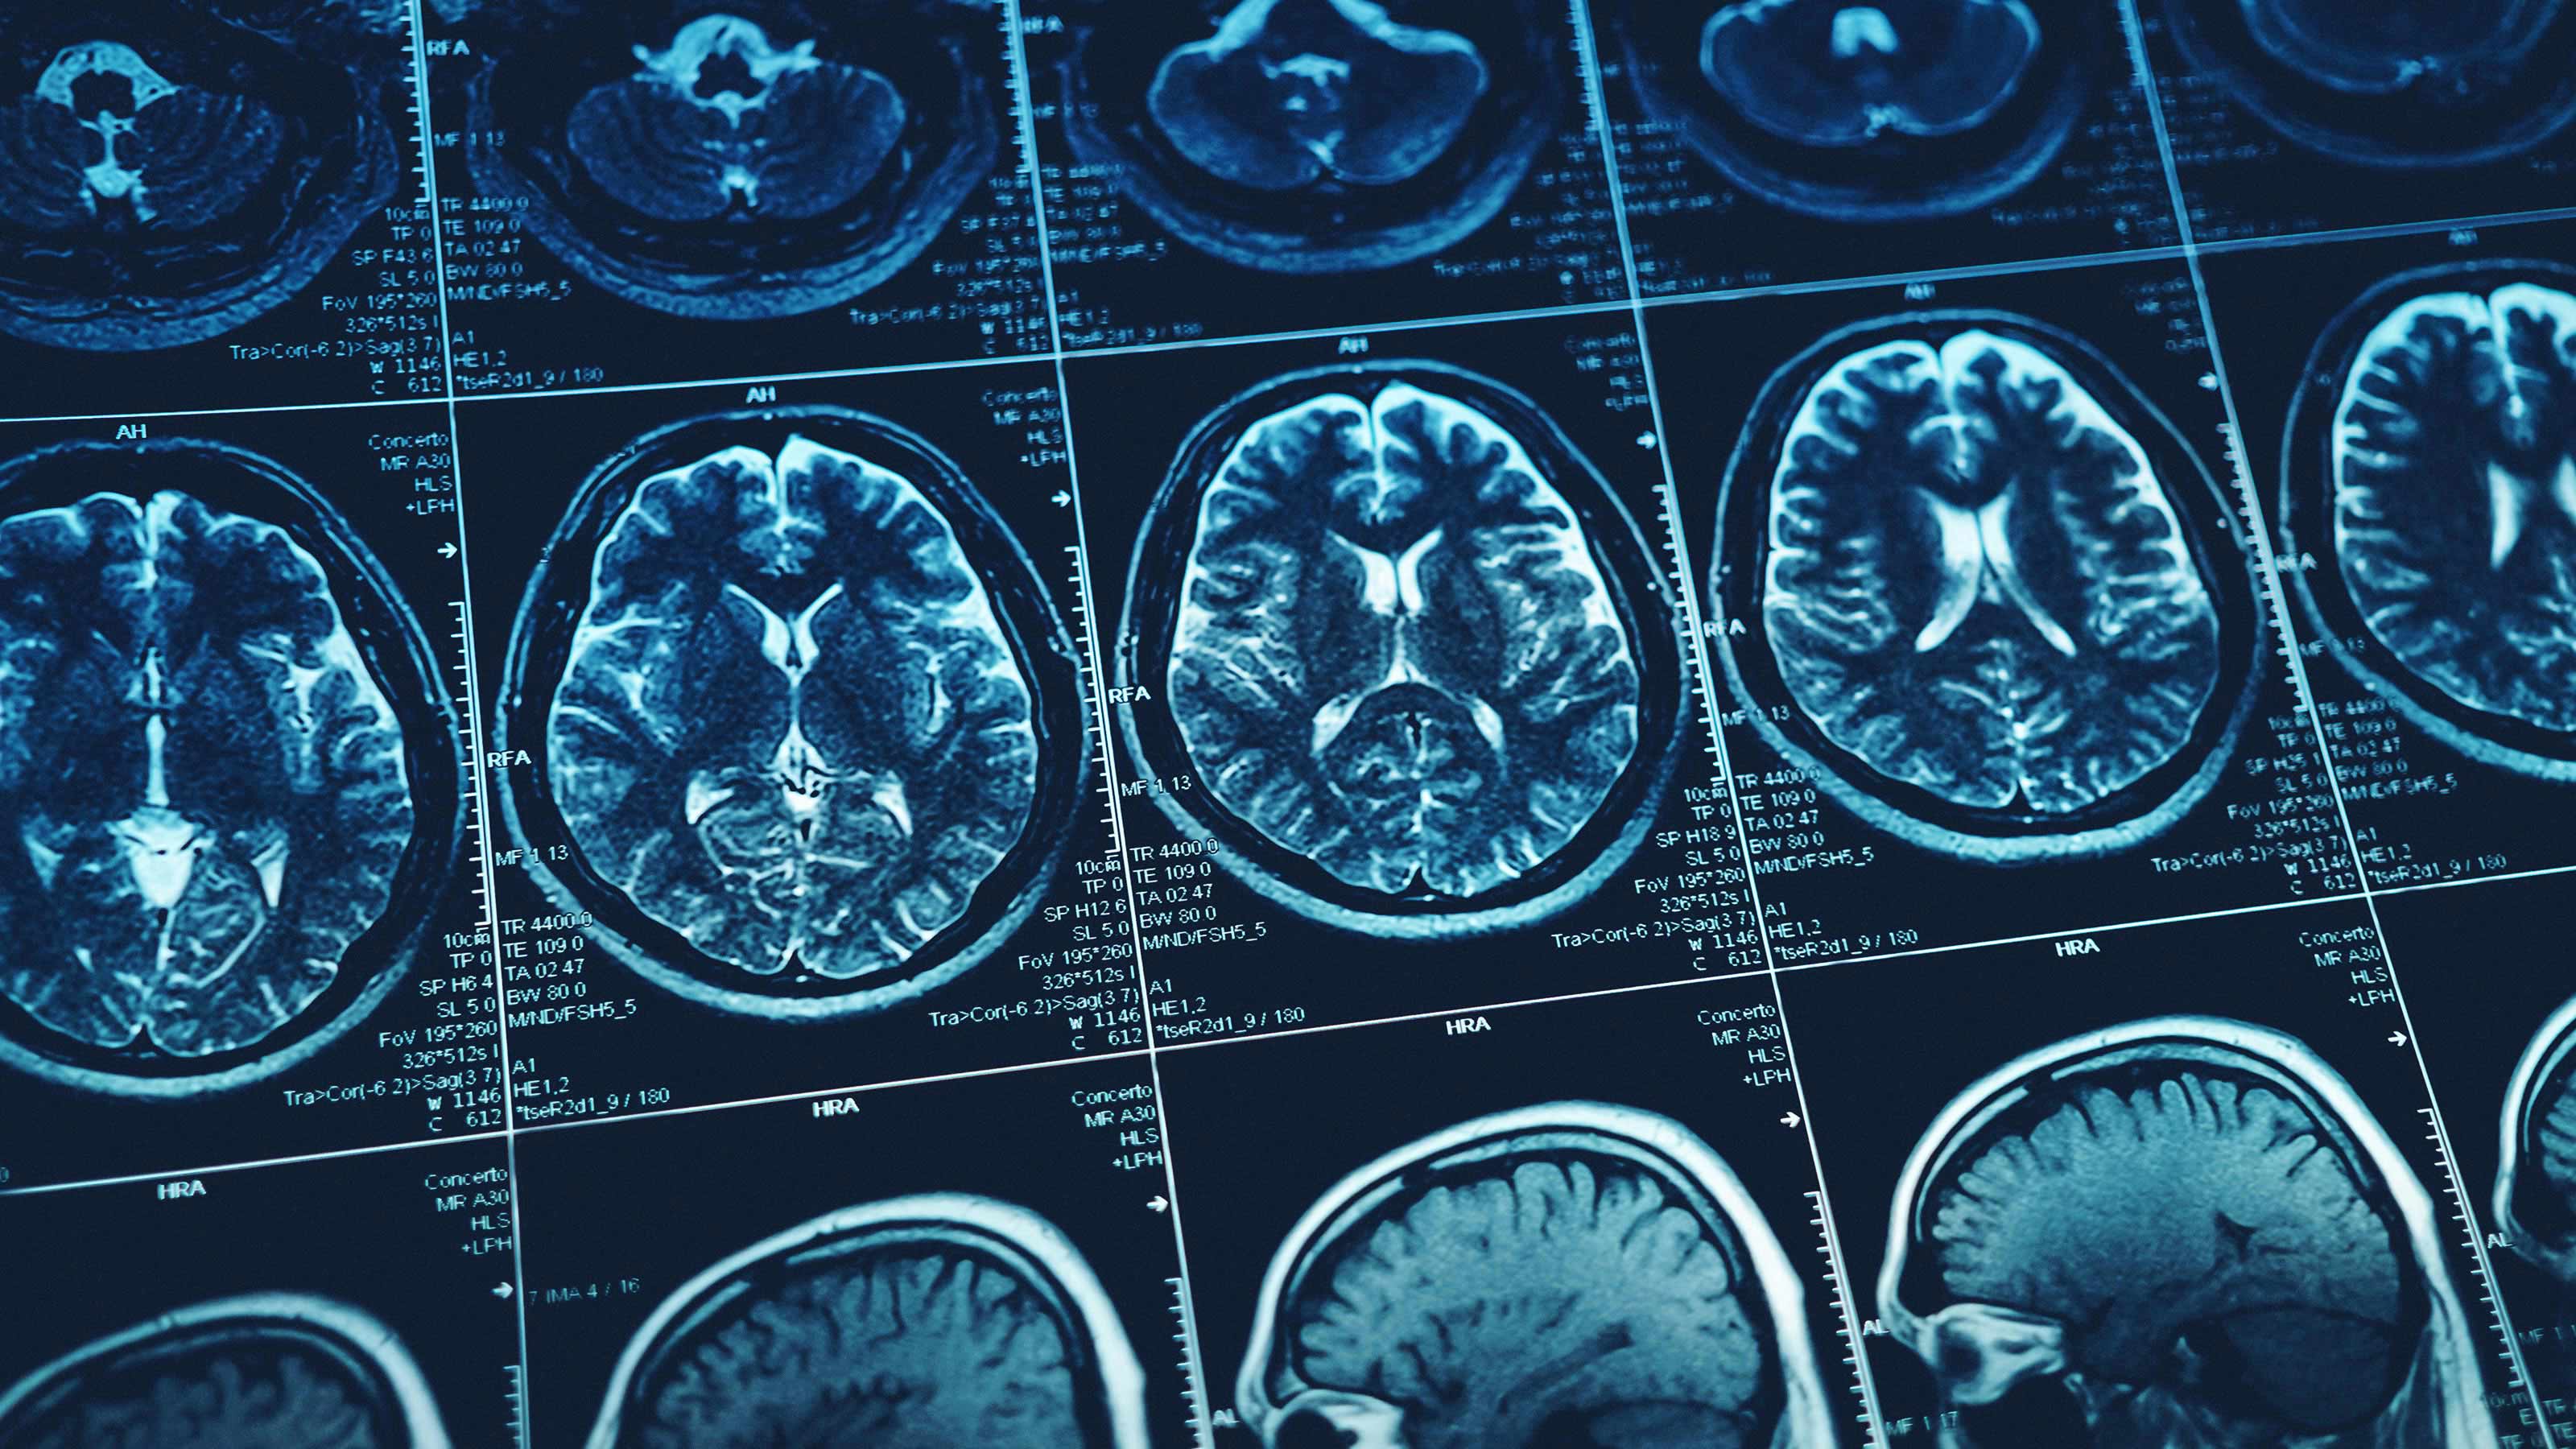

It all boils down to how our brains create and store memories. As Brunet explained in an interview with BBC News, the brain stores the factual elements of a memory in a region called the hippocampus and the emotions linked to the memory in the amygdala.